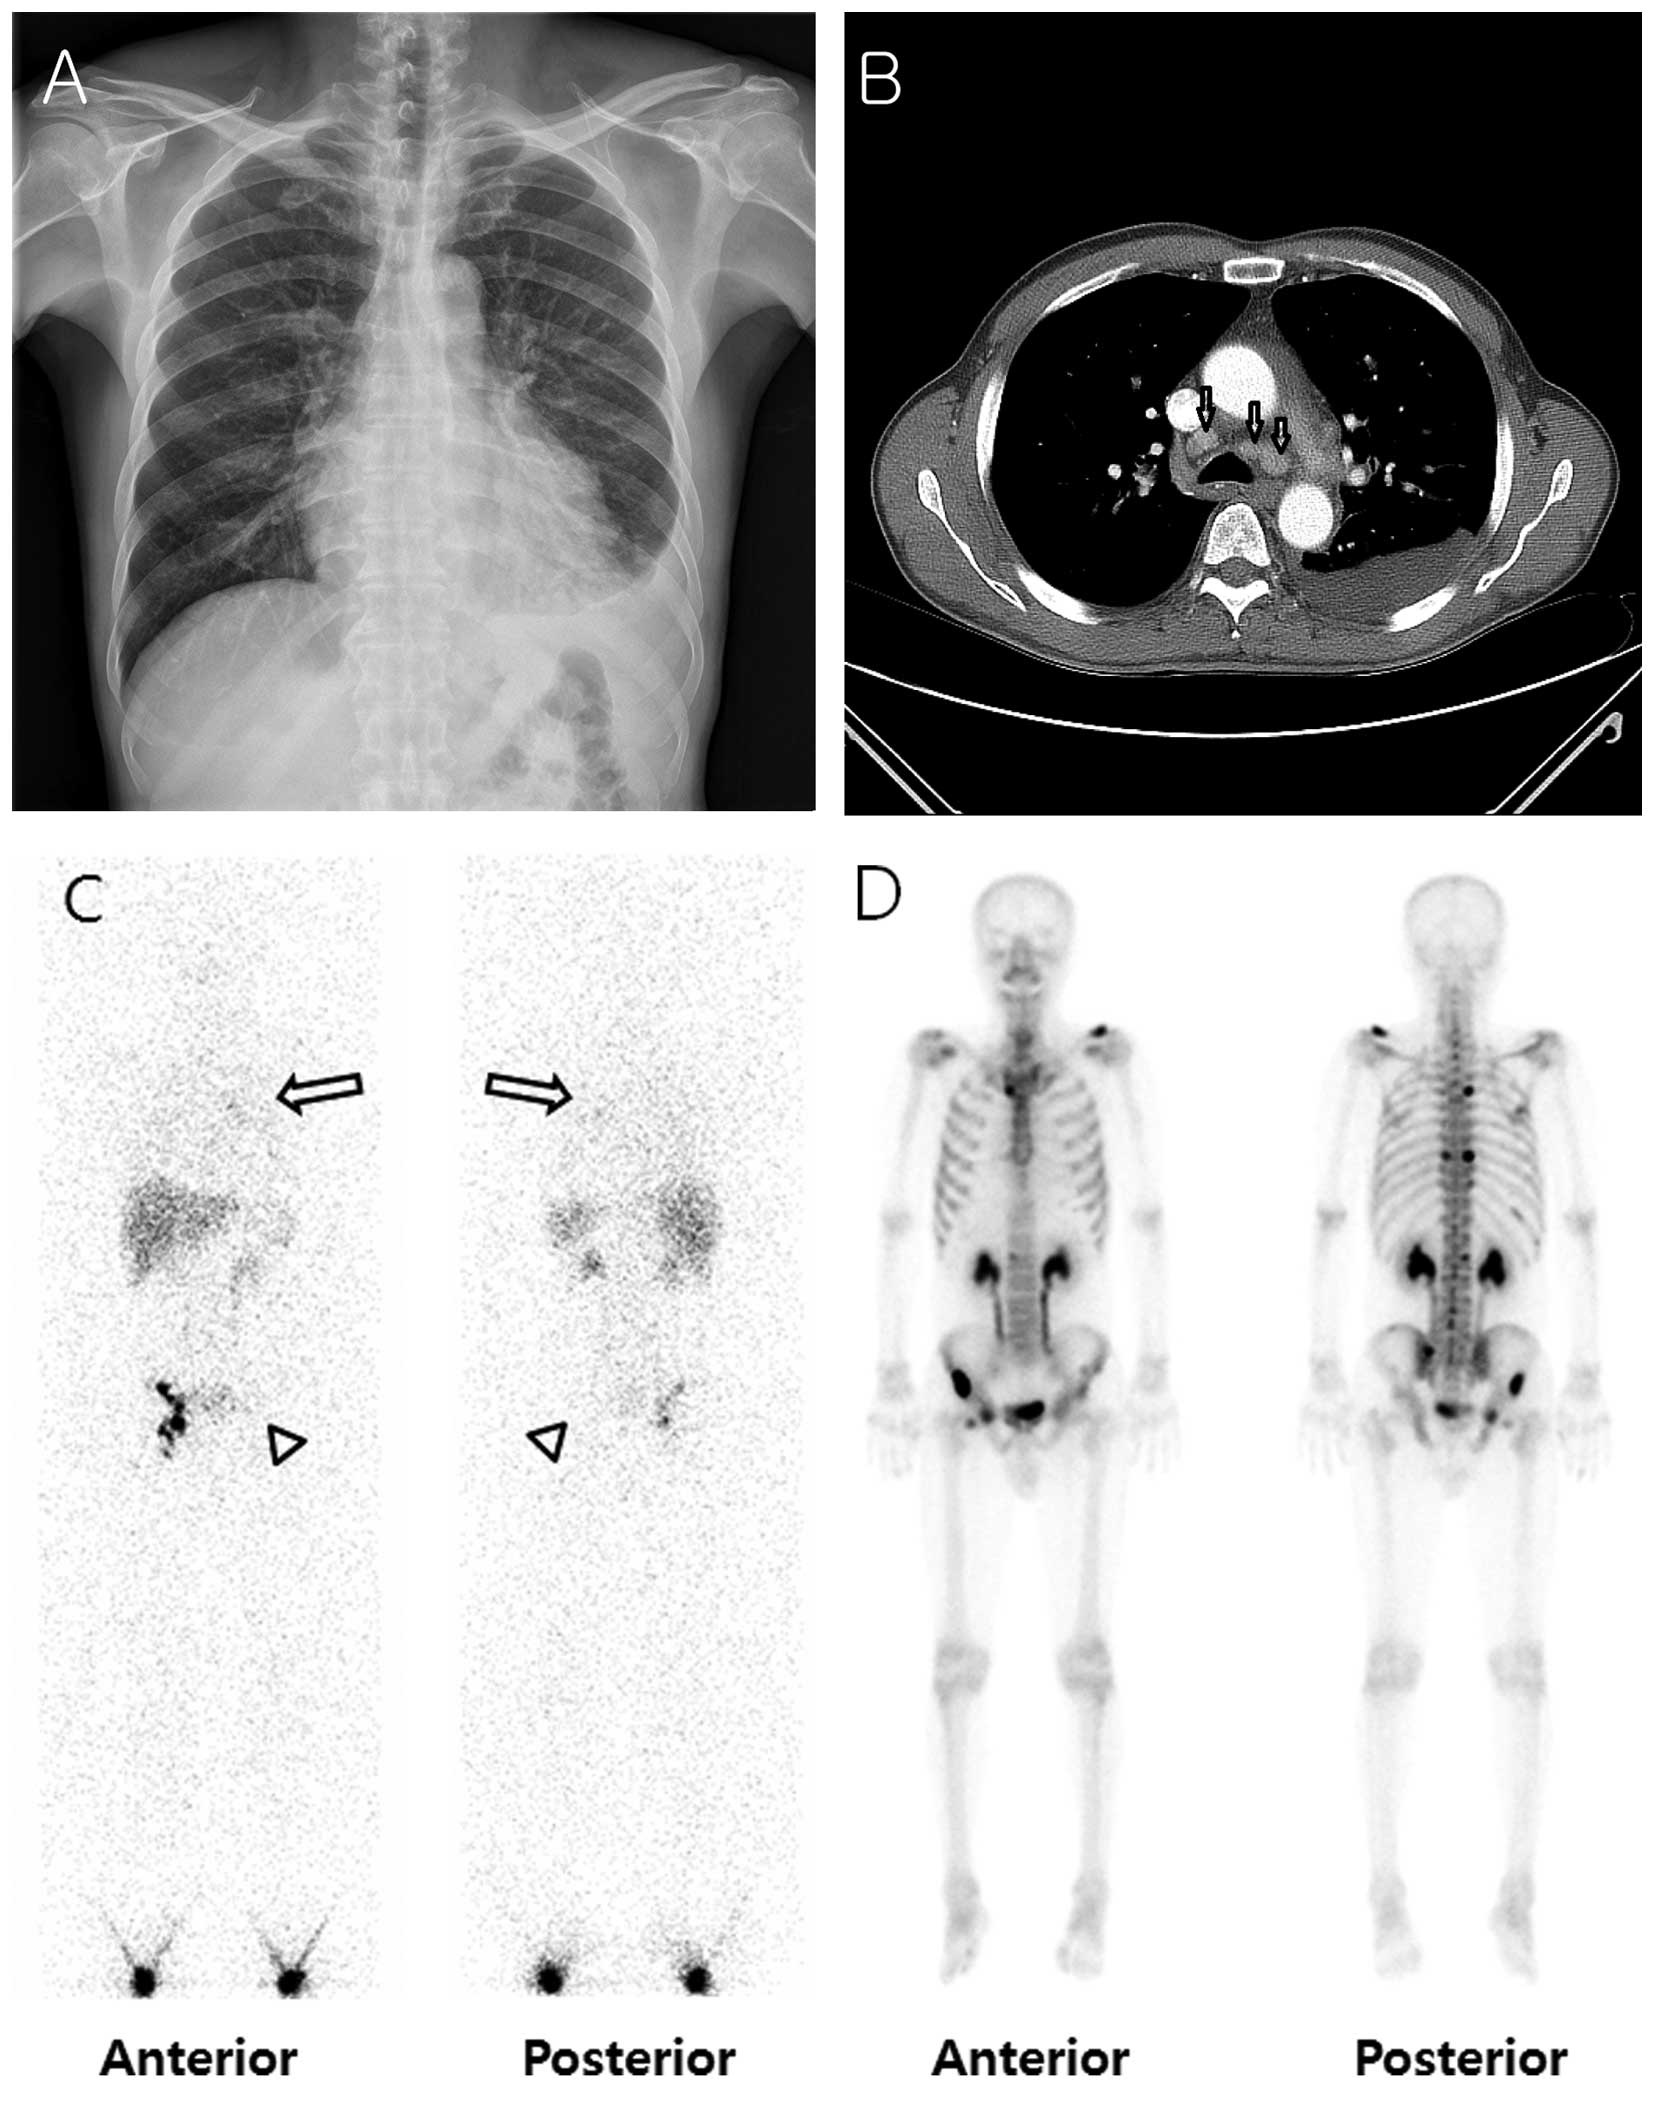

A 64-year-old Asian man visited the emergency room with dyspnea. The patient's medical history was unremarkable, with the exception of being a current smoker with a 20 pack-year history. Radiographic images, including computed tomography scan of the chest, revealed a left pleural effusion, pericardial effusion, and enlarged lymph nodes in the left supraclavicular/posterior neck/axillary area, right upper paratracheal area, subcarinal area, and bilateral lower paratracheal areas (Fig. 1A and B). Thoracentesis was performed and fluid analysis revealed a chylothorax, in which the triglyceride level was 244 mg/dl (normal range, <50 mg/dl). Whole-body lymphoscintigraphy revealed faint tracer accumulation activity in the medial portion of the left hemithorax, where the pleural effusion was present (Fig. 1C). Considering that the patient had never received thoracic surgery or experienced trauma, malignancy was suspected. Pleural fluid cytology revealed numerous mononuclear leukocytes and some reactive mesothelial cells, but did not show any evidence of malignancy. The serum PSA level was elevated to 194.6 ng/ml (normal range, 0–3 ng/ml).

Figure 1.

Chest radiography, chest computed tomography (CT), whole-body lymphoscintigraphy and bone scan images at diagnosis. (A) Chest radiography showing left pleural effusion. (B) Chest CT revealing mediastinal lymph node metastatic nodules (arrows) and left pleural effusion. (C) Whole-body lymphoscintigraphy image CAPTURED 2 h after radiotracer injection, revealing faint tracer accumulation activity in the medial portion of the left hemithorax, where pleural effusion was present (arrows). Tracer activity is absent in the left ilioinguinal chain (arrowheads). (D) Bone scan showing multiple bone metastases in the left clavicle, right ribs, thoracolumbar spine, bilateral pelvic bones and right femur.

A prostate biopsy revealed adenocarcinoma of the prostate gland. A bone scan was performed for staging, which revealed multiple bone metastases (Fig. 1D). Therefore, the chylothorax was considered to have resulted from thoracic duct obstruction by enlarged lymph node metastasis from prostate cancer. Androgen deprivation therapy (ADT) was initiated, with simultaneous administration of goserelin and anti-androgen. After 3 months, the amount of pleural effusion had decreased (Fig. 2A) and the serum PSA level decreased from 194.6 to 31.68 ng/ml following ADT. A bone scan performed 8 months after the initiation of ADT revealed that the intensities of multiple bone uptakes had decreased significantly when compared to the initial scan (Fig. 2B). The patient is undergoing regular follow-up at our outpatient clinic for 1 year after diagnosis and has not reported experiencing any further discomfort.